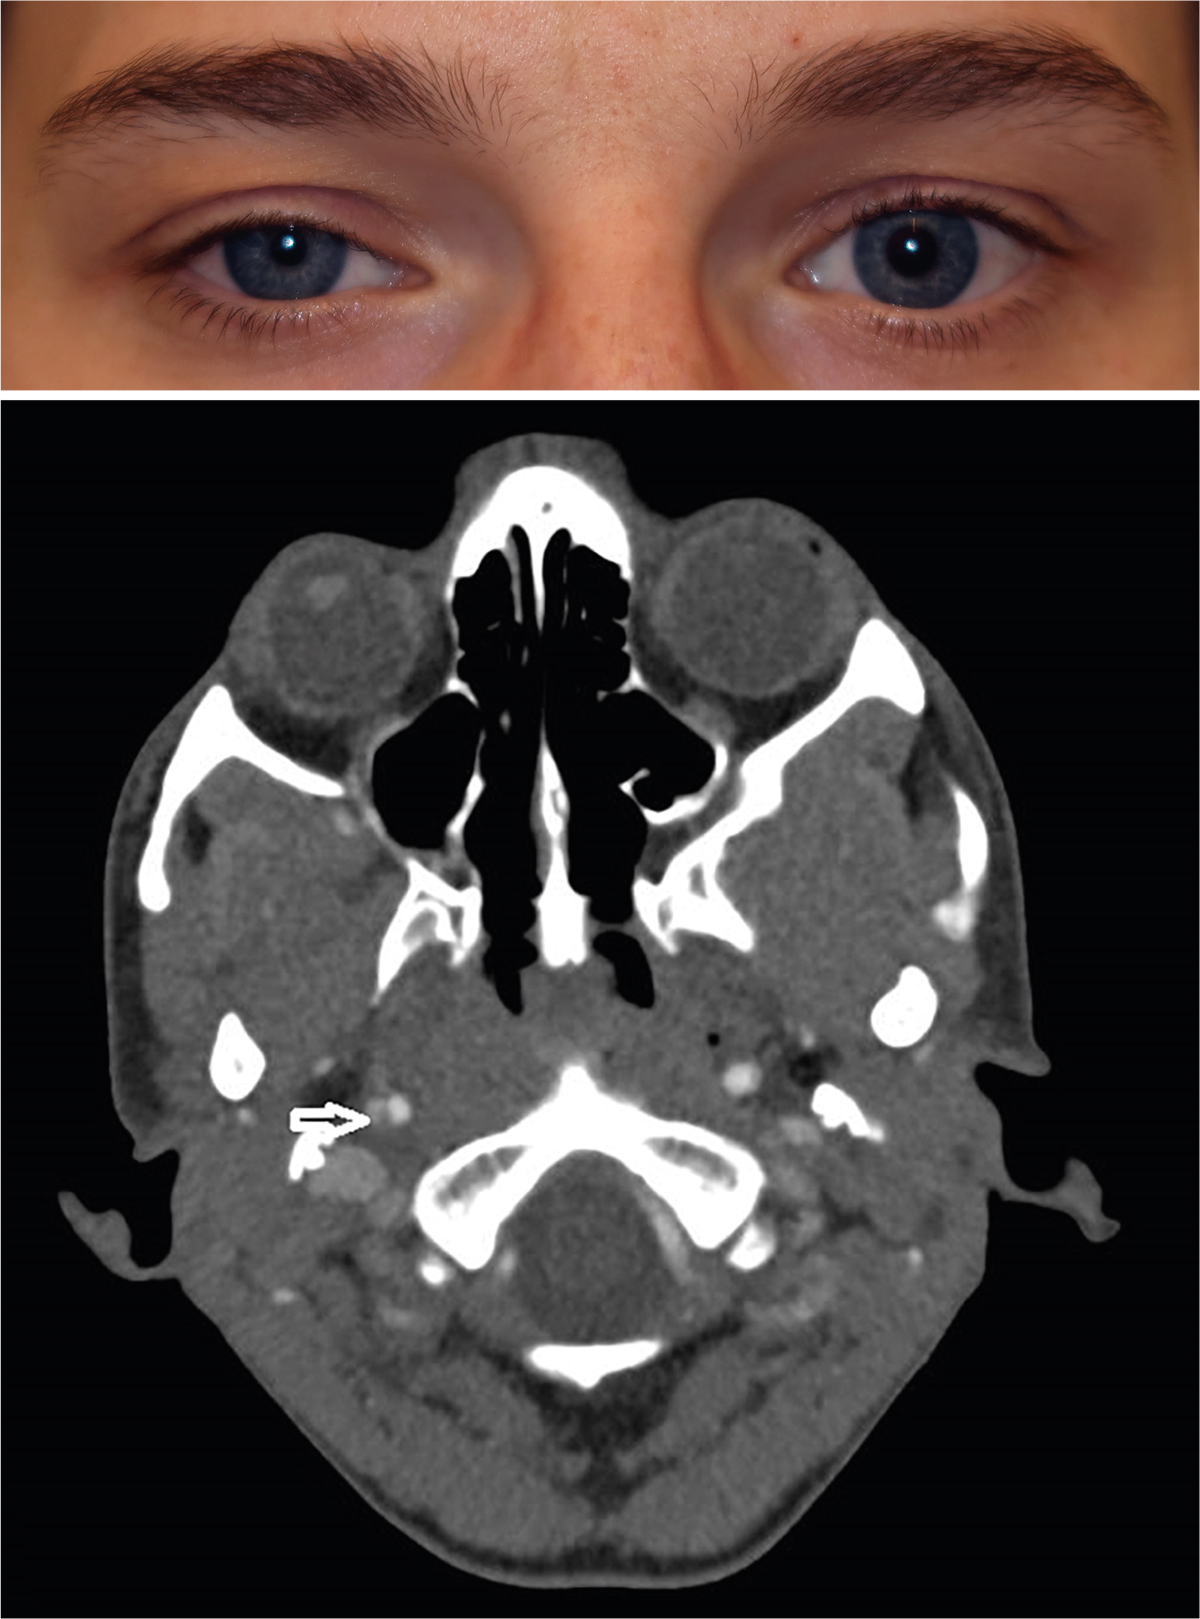

Horner Syndrom Durch Zähne . (PDF) Horner Syndrom infolge CarotisDissektion Was ist das Horner-Syndrom? Welche Symptome treten auf? Was sind die Ursachen? Wie wird das Horner-Syndrom behandelt? Wie ist die Prognose? Mehr erfahren! Horner's syndrome is a rare neurological disorder characterized by a disruption in the sympathetic nerve pathway, leading to a triad of ptosis, miosis and anhidrosis on the affected side of the face.

Source: unettyskm.pages.dev Horner Syndrom Lexikon der Augenheilkunde , Horner's syndrome is a rare neurological disorder characterized by a disruption in the sympathetic nerve pathway, leading to a triad of ptosis, miosis and anhidrosis on the affected side of the face. Das Sichtfeld wird durch das Horner-Syndrom in einigen Fällen auch verkleinert, sodass es zu Einschränkungen im dreidimensionalen Sehen kommen kann

Source: providenrad.pages.dev HornerSyndrom (HornerTrias) »Ursachen, Symptome, Prognose , Das Horner-Syndrom entsteht üblicherweise durch Lähmung der durch den Sympathikus innervierten glatten Augenmuskulatur Das Horner-Syndrom wird durch eine Schädigung des Nervensystems verursacht und hat typische Erscheinungsformen